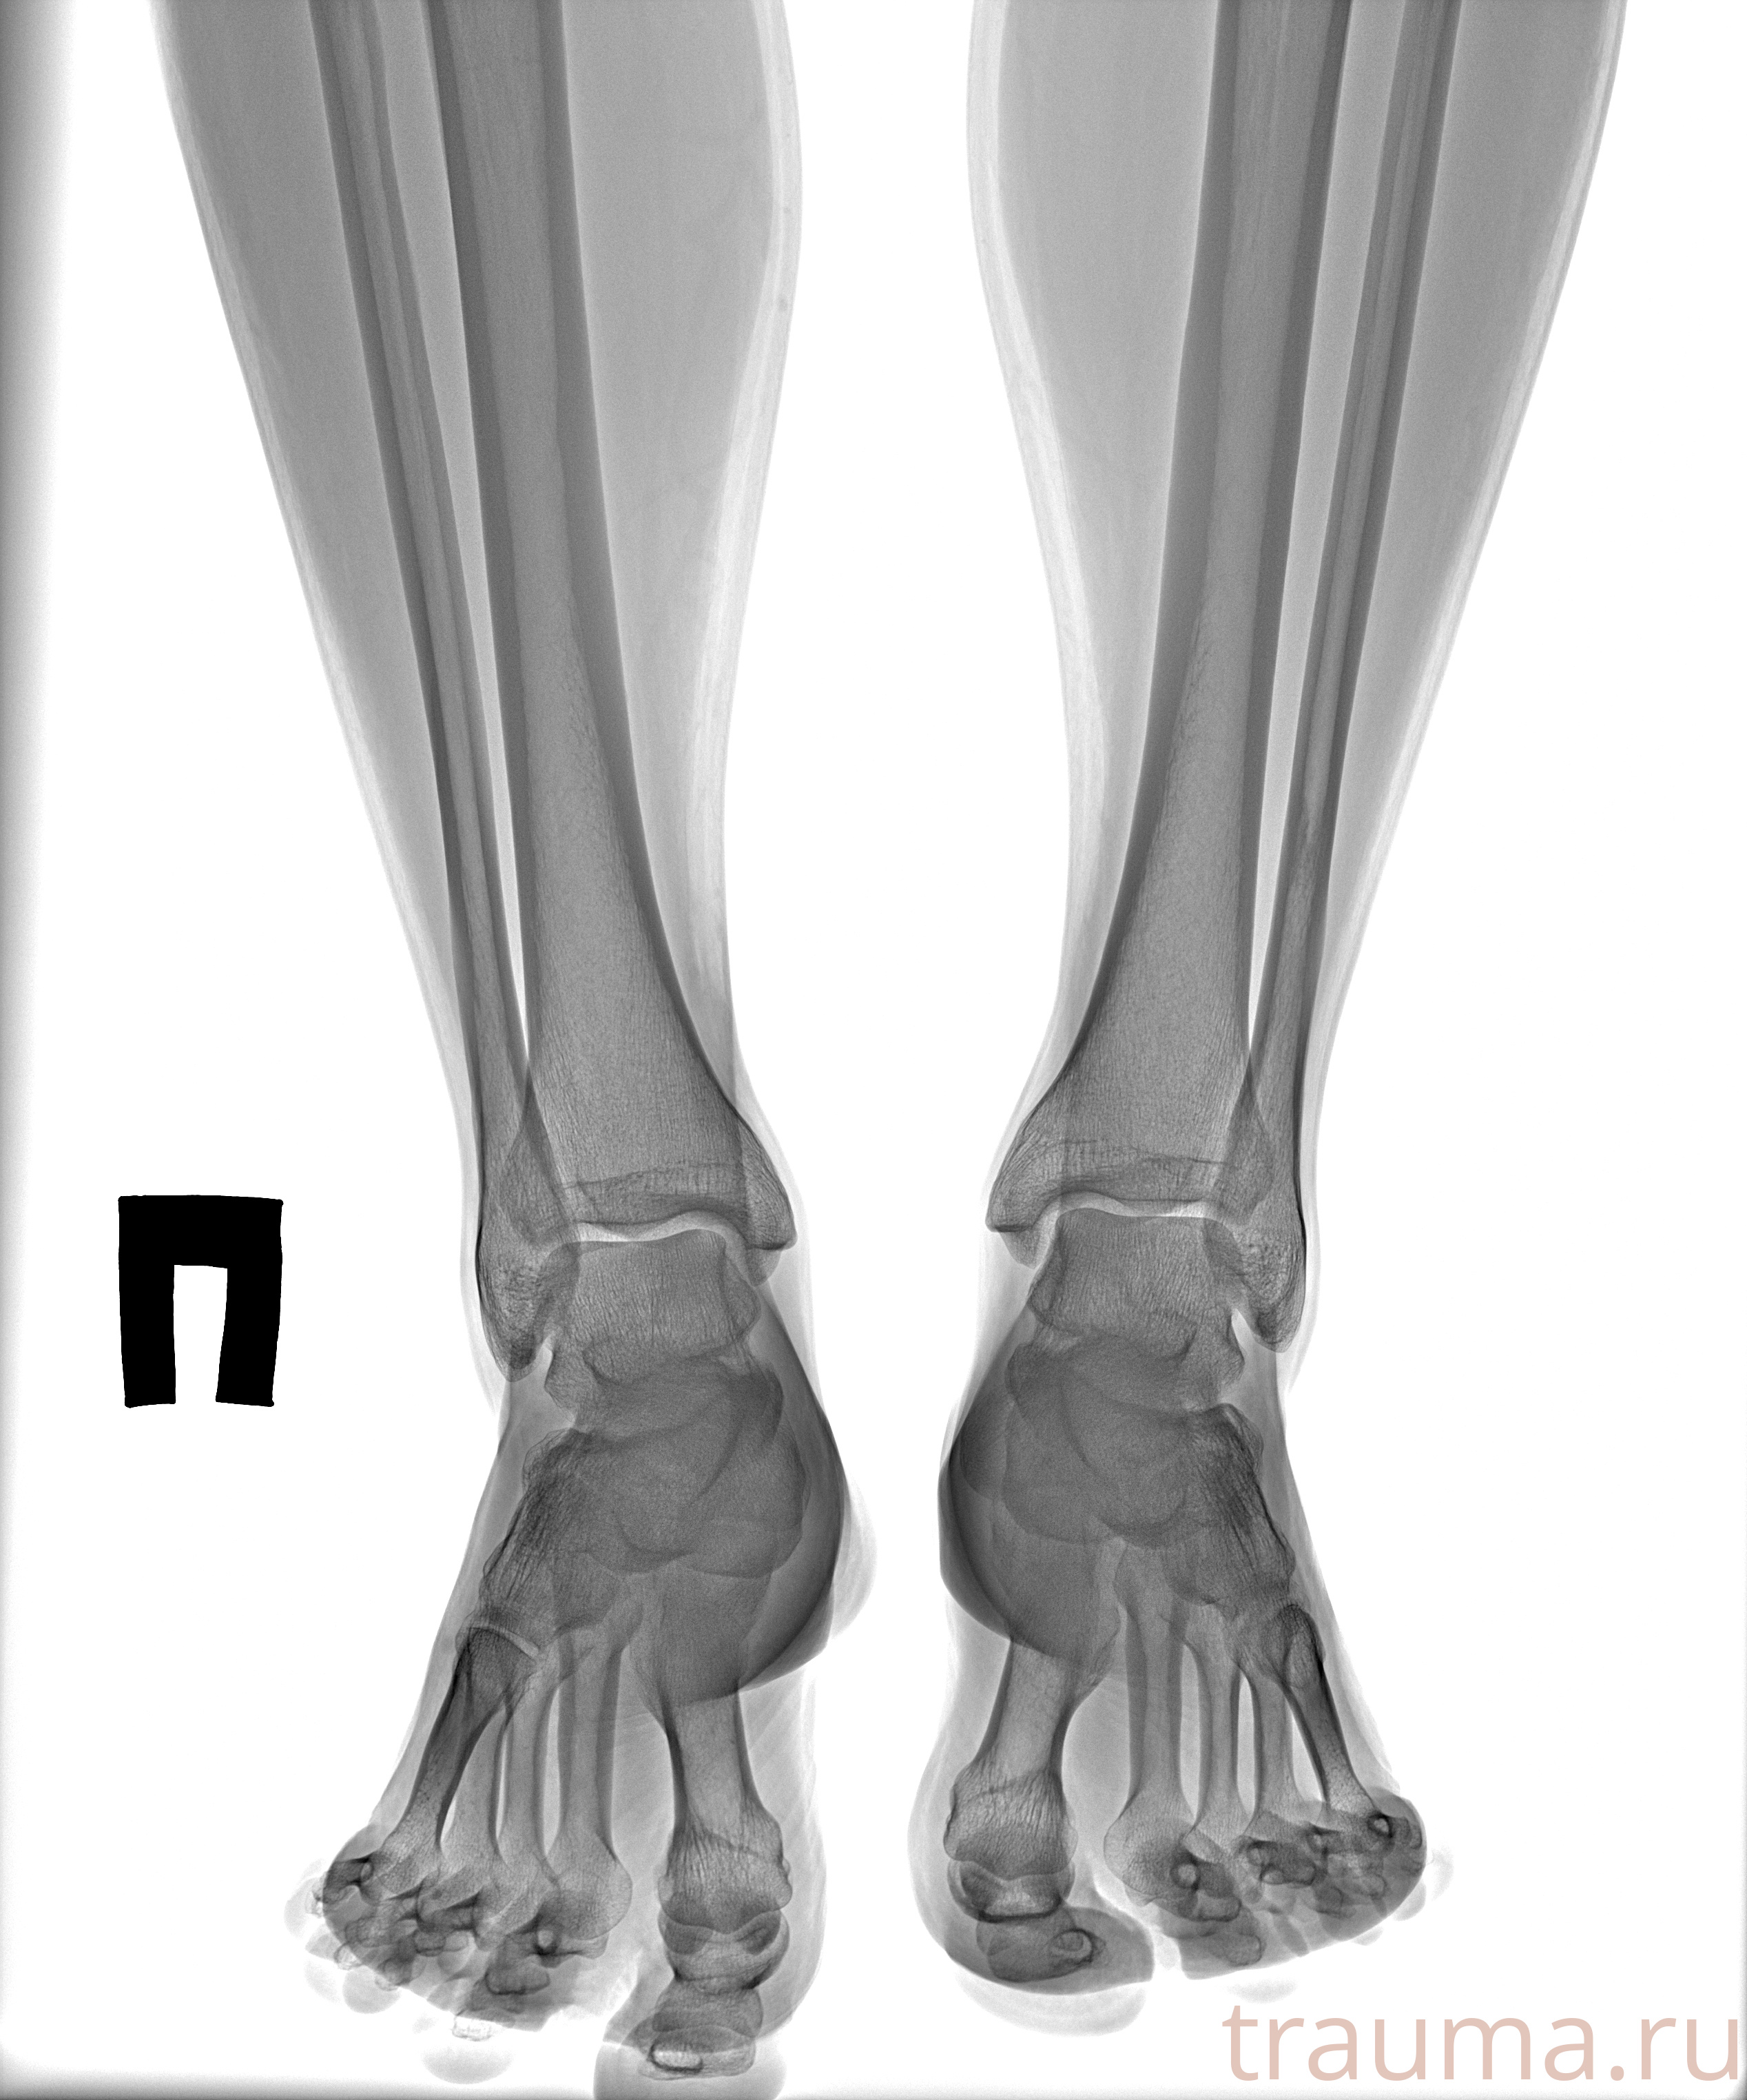

Рентген на дому: по вашему адресу приезжает врач-рентгенолог, травматолог-ортопед с мобильным рентгеновским аппаратом, проводит диагностику травмы или заболевания, делает необходимые рентгенограммы, дает рекомендации по дальнейшему лечению. Получить качественные снимки в домашних условиях возможно благодаря уникальной методике, разработанной МосРентген Центром для института  Склифосовского